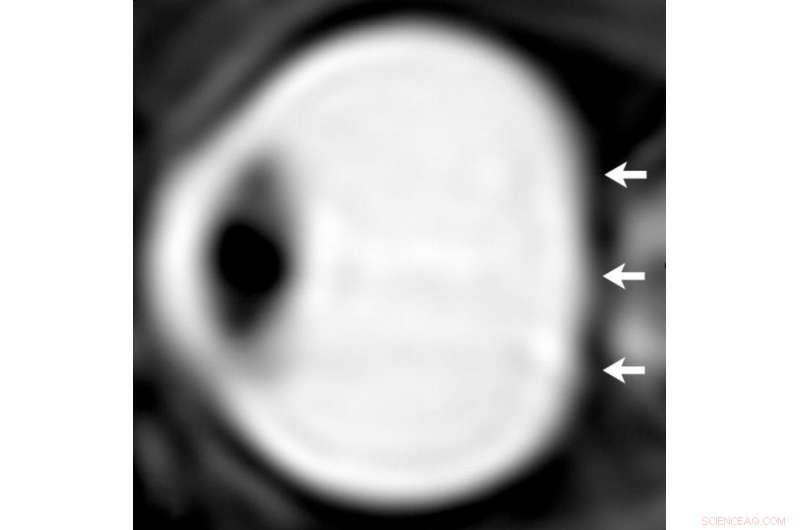

From a study of astronauts in 2012, sagittal oblique T2-weighted MR image of left eye before long-term flight. Note convexity of posterior globe (arrows). Credit: Radiological Society of North America

To learn more about the role of CSF in spaceflight-induced visual impairment and eye changes, Dr. Alperin and colleagues performed high-resolution orbit and brain MRI scans before and shortly after spaceflights for seven long-duration mission ISS astronauts.

They compared results with those from nine short-duration mission space shuttle astronauts. Using advanced quantitative imaging algorithms, the researchers looked for any correlation between changes in CSF volumes and the structures of the visual system.

The results showed that, compared to short-duration astronauts, long-duration astronauts had significantly increased post-flight flattening of their eyeballs and increased optic nerve protrusion. Long-duration astronauts also had significantly greater post-flight increases in orbital CSF volume, or the CSF around the optic nerves within the bony cavity of the skull that holds the eye, and ventricular CSF volume—volume in the cavities of the brain where CSF is produced. The large post-spaceflight ocular changes observed in ISS crew members were associated with greater increases in intraorbital and intracranial CSF volume.